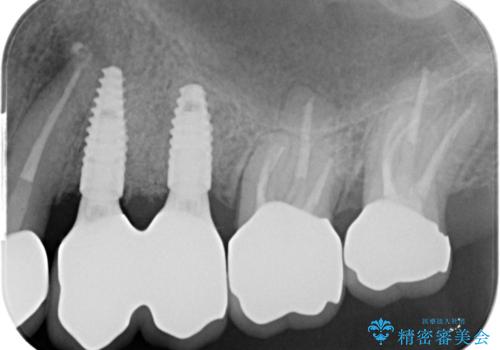

銀歯を除去したのち、虫歯を丁寧に除去し、歯を残せるのかどうかをしっかりと評価し、長期的な予後を見据えた虫歯治療を行っていきます。

- 154万円(インプラント×2・チタンカスタムアバットメント×2・ジルコニアクラウン×6・仮歯×6)費用は治療当時の料金となります

銀歯の下で虫歯が再発していた歯は、無理に残しても割れてしまう可能性が非常に高いと考えたため、相談の上抜去を行いインプラント治療を行っていくこととしました。